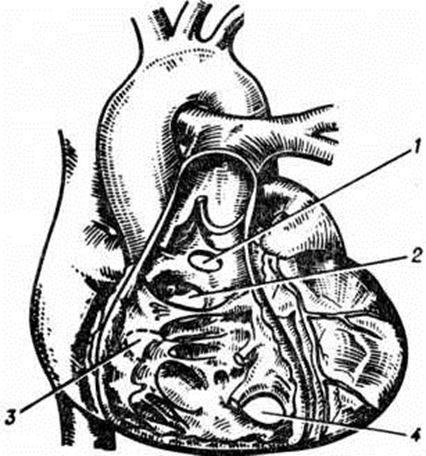

Наблюдается тенденция к возрастанию частоты пороков развития, особенно в развитых странах, со второй половины 20 в. Чаще других Пороки сердца врождённые встречаются открытый артериальный проток (смотри полный свод знаний), Фалло тетрада (смотри полный свод знаний) и дефекты межпредсердной и межжелудочковой перегородок. Смертность от Пороки сердца врождённые наиболее велика в раннем детском возрасте. Если не проводится оперативное лечение, то, по усреднённым данным, около 40% детей, родившихся с Пороки сердца врождённые, умирает в возрасте до 3 лет; по данным Банкла, из 1000 умерших с Пороки сердца врождённые 67% погибли в течение первого года жизни. При некоторых Пороки сердца врождённые, связанных с задержкой развития и обнаруживаемых у новорождённых, в части случаев отмечается спонтанное самоизлечение (завершение формообразования) в постнатальном периоде. Частота самоизлечения и смертность с возрастом уменьшаются. Этиология даже одинаковых по морфологическому типу Пороки сердца врождённые, по-видимому, так же разнородна, как и этиология пороков развития вообще. В одних случаях решающее значение имеет наследственность, а также хромосомные аномалии в связи с гормональным дисбалансом и другими эндогенными причинами. В других случаях основную роль играют экзогенные факторы, приводящие к задержке или остановке развития морфологических структур сердца и сосудов в любой фазе органогенеза или же тератогенные воздействия в критические его периоды (ионизирующее излучение, интоксикации, вирусные инфекции, применение некоторых лекарств в период беременности и так далее). Генетическая природа части Пороки сердца врождённые находит отражение в известных хромосомных аномалиях, приводящих к развитию типичных сочетаний: синдрома Дауна и атриовентрикулярного канала, синдрома Марфана и аортального порока и другие Этиологическая роль наследственности, повидимому, ограничена. Е. Г. Костылев (1976) при изучении 2000 семей больных, оперированных по поводу Пороки сердца врождённые, смог установить роль наследственных факторов только в 29 семьях. Это обстоятельство подчёркивает важность изучения этиологической роли экзогенных воздействий, особенно в свете уже установленного тератогенного влияния ряда лекарств, применяемых в первом триместре беременности и перенесённых в этот период инфекционных заболеваний, например, краснухи. Классификация. Многообразие форм Пороки сердца врождённые с разнородными сочетаниями аномалий сердца и сосудов затрудняет создание их классификации, унифицированной по группе однородных признаков, включающей все известные формы Пороки сердца врождённые и равно удовлетворяющей специалистов теоретической и практической медицины. Этим объясняется большое число классификаций Пороки сердца врождённые По состоянию функции кровообращения все Пороки сердца врождённые можно разделить на нарушающие эту функцию и на практически не изменяющие её. К последней группе относятся некоторые изолированные формы аномалии положения (декстрокардия, синистрокардия) и эктопии сердца, изолированное расширение лёгочного ствола (смотри полный свод знаний), неосложнённые врождённые дефекты перикарда (смотри полный свод знаний) и некоторые дивертикулы сердца. Большинство классификаций Пороки сердца врождённые создавалось с учётом клинических потребностей, то есть относилось прежде всего к порокам, нарушающим гемодинамику. Первые клинические классификации основывались на разделении Пороки сердца врождённые в зависимости от наличия и степени стойкости цианоза (смотри полный свод знаний). Так, одна из ранних клинических классификаций, предложенная Эбботтом и Досоном (М. Е. Abbott, W. Т. Dawson, 1924), состояла в разделении Пороки сердца врождённые на три группы: со стойким цианозом, с факультативным цианозом и без цианоза, причём в первой группе Пороки сердца врождённые дополнительно подразделялись на три подгруппы по степени выраженности цианоза. В какой-то мере классификация Пороки сердца врождённые на «синие» и «бледные» пороки ориентирует диагностику на определённые морфологические типы Пороки сердца врождённые, а степень цианоза во многих случаях соответствует серьёзности врождённой аномалии. В более поздних классификациях, в частности предложенных Тауссиг (Н. В. Taussig, 1947) и Донзело (Е. Donzelot) с соавторами (1954), учитывались патофизиологические механизмы гемодинамических нарушений: Тауссиг подчеркнула патогенетическую и прогностическую роль изменений при Пороки сердца врождённые лёгочного кровотока, а Донзело обособил группу пороков, характеризующихся прямым венозно-артериальным сообщением, выявление которого инструментальными методами более информативно для диагностики порока, чем цианоз. Значение изменений гемодинамики в малом круге кровообращения как для клинической характеристики типа порока, так п для его диагностики и установления показаний к оперативному лечению нашло отражение почти во всех последующих классификациях Пороки сердца врождённые, в частности в классификации, модифицированной П. А. Куприяновым, в которой Пороки сердца врождённые разделялись на три группы: с нормоволемией, гиперволемией и гиповолемией малого круга (дополнительно выделялись подгруппы «с цианозом» и «без цианоза»). Этот принцип в той или иной мере сохранен в большинстве современных классификаций, в том числе в классификациях Н. М. Амосова, В. И. Бураковского, Б. А. Королева, Е. Н. Мешалкина, В. С. Савельева, В. И. Францева и другие Для целей хирургической практики в этих классификациях используются как морфологические, так и функциональные признаки Пороки сердца врождённые, а в некоторых из них классифицируются также степени гемодинамических нарушений. Классификации отдельных форм Пороки сердца врождённые также подчинены обычно практическим целям и строятся с учётом ведущих гемодинамических признаков порока, выявляемых определёнными диагностическими методиками. Так, например, дефект межжелудочковой перегородки характеризуется разными исследователями по таким критериям гемодинамических нарушений, как направление сброса крови (лево-правый, перекрёстный, право-левый), величина сброса, степень гиперволемии или степень гипертензии малого круга кровообращения, величина лёгочного сопротивления и так далее Не считая некоторых различий в отдельных классификациях, клинически значимые формы Пороки сердца врождённые подразделяют в соответствии с гемодинамическими нарушениями в основном на следующие группы. Пороки с неизменённым или малоизменённым лёгочным кровотоком. Аномалии дуги аорты и её ветвей, отсутствие дуги аорты, стеноз аорты, коарктация аорты взрослого типа, атрезия аортального клапана, митральный стеноз, митральная атрезия, недостаточность митрального клапана, недостаточность клапана лёгочного ствола, трёх-предсердное сердце, пороки венечных артерий сердца, пороки проводящей системы сердца. Пороки с гиперволемией малого круга кровообращения. 1. Не сопровождающиеся ранним цианозом: открытый артериальный проток, дефект межпредсердной перегородки, синдром Лютамбаше, дефект межжелудочковой перегородки, комплекс Эйзенменгера, аорто-лёгочный свищ, коарктация аорты детского типа. 2. Сопровождающиеся цианозом: трикуспидальная атрезия с нормальным калибром лёгочного ствола и большим дефектом межжелудочковой перегородки, а также открытый артериальный проток с током крови из лёгочного ствола в аорту и комплекс Эйзенменгера при выраженной гипертензии в сосудах малого круга. Пороки с гиповолемией малого круга кровообращения. 1. Не сопровождающиеся цианозом: изолированный стеноз лёгочного ствола (инфундибулярный и клапанный). 2. Сопровождающиеся цианозом: триада Фалло, тетрада Фалло, пентада Фалло, трикуспидальная атрезия с сужением лёгочного ствола или малым дефектом межжелудочковой перегородки, аномалия Эбштейна, гипоплазия правого желудочка. Комбинированные пороки: полная транспозиция аорты и лёгочного ствола, корригированная транспозиция аорты и лёгочного ствола, синдром Тауссиг — Бинга, отхождение аорты и лёгочного ствола от правого желудочка, отхождение аорты и лёгочного ствола от левого желудочка, общий артериальный ствол, трёх-камерное сердце с единым желудочком. К этой группе относятся Пороки сердца врождённые, при которых выявляются нарушения взаимоотношений между различными отделами сердца и крупными сосудами. При этом возможны разные варианты соотношений кровотока в малом и большом круге кровообращения или нарушения кровотока. Отдельные группы врождённых пороков сердцаПоскольку клинические классификации Пороки сердца врождённые в известной мере условны и, как правило, не охватывают все встречающиеся аномалии, описание отдельных пороков дано в алфавитном порядке. Аномалии вен большого круга кровообращения. Нарушения нормального развития венозной системы большого круга кровообращения могут привести к сохранению (вместо облитерации) левого кювьерова протока (общая кардинальная вена). В этом случае у больного сохраняется левосторонняя вертикальная вена (или левая верхняя полая вена), которая впадает в коронарный синус и собирает венозную кровь из левой верхней половины тела. Если при этом сохраняется левая плечеголовная вена, то вертикальная вена сообщается с правой верхней полой веной. Очень редко происходит аномальная облитерация правого кювьерова протока, и тогда венозная кровь верхней половины тела возвращается в сердце через левую вертикальную вену. При отсутствии нижней полой вены печёночные вены самостоятельно впадают в правое предсердие. Венозная кровь нижней половины тела протекает через расширенную непарную вену, впадающую в верхнюю полую вену. Очень редко полые вены впадают в левое предсердие. При этом обязательно сохраняется открытое овальное окно, возможен дефект межжелудочковой перегородки или открытый артериальный проток. Аномалии венозного притока к сердцу сами по себе не сопровождаются нарушениями гемодинамики, за исключением тех вариантов, когда вены впадают в левое предсердие; в этих случаях больные цианотичны, правый желудочек гипоплазирован. Коррекцию аномалии производят путём перемещения устья полых вен в правое предсердие или пластикой межпредсердной перегородки с использованием трансплантата из аутоперикарда. Аномалии дуги аорты и её ветвей. Порок связан с нарушением эмбриогенеза (вместо регрессии некоторые отделы артерий жаберных дуг сохраняются). В норме левая лёгочная артерия формируется из проксимальной части шестой дуги. Из её дистальной части слева образуется артериальный проток (смотри полный свод знаний). Дистальная часть его справа обычно регрессирует, исчезая полностью или сохраняясь в виде рудимента и очень редко как правосторонний открытый артериальный проток. Четвертая левая дуга превращается в восходящую часть нормальной аорты и соединяется с устьем левой общей сонной артерии (сегментом третьей дуги). Нарушения механизма обратного развития восьмого сегмента дорсальной аорты слева или справа в сочетании с аномалией четвертой артериальной дуги (также справа и слева) приводит к формированию двойной дуги аорты с различным соотношением её частей, к сохранению билатерального артериального протока и необычному отхождению магистральных артерий (подключичных и сонных). Разнообразие сочетаний аномалий дуги аорты и магистральных сосудов велико (более 20 сочетаний). Однако в практическом отношении имеют значение лишь некоторые из них (смотри рисунок 4): двойная дуга аорты (с узкой передней левой и широкой задней правой дугой, с широкой передней левой и узкой задней правой дугой), правая дуга аорты с левым артериальным протоком, аномальное отхождение левой общей сонной артерии (со смещением её устья вправо), аномальное расположение плечеголовного ствола или его ветвей (со смещением устьев вправо), левая дуга аорты с расположенным справа артериальным протоком, крайне левое отхождение правой подключичной артерии, правая аортальная дуга с расположением нисходящей грудной аорты слева, левая аортальная дуга с лежащей справа нисходящей грудной аортой. Клиническая картина независимо от вида аномалий связана со сдавлением трахеи или (и) пищевода. Степень сдавления определяет тяжесть течения болезни (от лёгкой до выраженной). Затруднения проглатывания и особенно дыхания у детей являются наиболее частыми признаками порока. Стридорозные явления (смотри полный свод знаний: Стридор) могут резко усиливаться и вызывать приступы тяжёлой одышки. Возможна аспирация рвотных масс. Разгибание головы иногда даёт облегчение. Иногда двойная дуга аорты клинически не проявляется и обнаруживается только во время аутопсии. Наиболее ценным диагностическим исследованием является рентгенологическое. Томография трахеи, трахеобронхография, контрастирование пищевода (особенно в косых и боковых проекциях) позволяют правильно распознать порок. Кинотрахеограмма помогает выявить необычные движения трахеи и моменты её коллапса. При расположении грудной части аорты справа или слева пищевод может располагаться контрлатерально. В затруднительных случаях показана бронхоскопия и ретроградная аортография. Лечение только оперативное. Показания к нему определяются степенью сдавления трахеи и пищевода. Операция направлена на рассечение сосудистого кольца и высвобождение трахеи и пищевода. Так, при наличии двойной дуги одну из дуг (с меньшим диаметром) пересекают и накладывают сосудистый шов (смотри полный свод знаний). Точно такую же операцию производят при обнаружении артериального протока или его рудимента. Подключичную артерию, аномально проходящую позади пищевода и трахеи, отсекают и подшивают без натяжения к левой общей сонной артерии так, чтобы расширить сосудистое кольцо. Исходы операций, как правило, благоприятные. Аномалии коронарных артерий. Отхождение коронарных артерий от лёгочного ствола приводит к ишемии миокарда и сердечной недостаточности вскоре после рождения. Чаще правая коронарная артерия имеет нормальное положение и снабжает миокард через коллатерали. Кровоток в аномально отходящей левой коронарной артерии направлен ретроградно, в лёгочный ствол. Этот лево-правый шунт, как правило, небольшой. Левый желудочек дилатирован и фиброзно изменён, имеет парадоксальные сократительные движения и слабую сократительную способность. Во время физических нагрузок, даже малых, возникают типичные приступы стенокардии (смотри полный свод знаний). Сердце постепенно увеличивается. При инфаркте сосочковых мышц и развитии митральной недостаточности появляется интенсивный систолический шум. На ЭКГ характерные признаки ишемической болезни сердца (смотри полный свод знаний) или инфаркта миокарда (смотри полный свод знаний). Рентгенологические изменения: кардиомегалия, резкий венозный застой в лёгких. При катетеризации сердца и особенно при контрастном исследовании аорты и левого желудочка обнаруживаются только правая коронарная артерия, большой остаточный диастолический объем желудочка и его слабая сократительная деятельность. Иногда на снимках становится видимой левая коронарная артерия. Лечение оперативное: производят наложение аортокоронарного шунта с левой коронарной артерией, которую у самого устья перевязывают. Более перспективной операцией считают анастомозирование левой подключичной артерии с аномальной коронарной артерией. Однако эти операции не улучшают функции левого желудочка. Аномалии расположения сердца подразделяют на эктопии сердца и аномалии его внутригрудного расположения. К эктопиям сердца относят дислокацию, при которой часть сердца или все оно располагается внутри или вне средостения (смотри полный свод знаний); наблюдаются и другие эктопии: шейные, торакальные, торакоабдоминальные, абдоминальные. Смещённое сердце, покрытое перикардом или без него, может быть расположено на поверхности тела (при торакальной эктопии) или внутри серозной полости (при брюшной эктопии). Наиболее часто наблюдаются грудные эктопии, реже брюшные и очень редко шейные. Обычно эктопия сердца сопровождается другими Пороки сердца врождённые (дефекты перегородок, тетрада Фалло, полная транспозиция и другие), а также неправильным расположением брюшных органов. Согласно классификации Института сердечно-сосудистой хирургии имени акад. А. Н. Бакулева аномалии расположения сердца подразделяют в зависимости от локализации правого (венозного) предсердия, верхушки сердца, брюшных органов, а также пространственных соотношений желудочков сердца и предсердий. Расположение венозного предсердия определяется по отношению к средней линии и левому (артериальному) предсердию; в зависимости от этого сердце может быть право или лево-сформированным. Положение верхушки сердца по отношению к средней линии тела характеризуется как право или лево-расположенное. Таким образом, нормальное сердце обозначается как право-сформированное лево-расположенное. Согласно этому подразделению возможны 7 основных сочетаний аномального расположения сердца. Клинические, проявления порока могут быть различными. Обычно аномалии расположения сердца сами по себе не вызывают существенных нарушений в гемодинамике, однако их частные сочетания с другими Пороки сердца врождённые обусловливают патологический нарушения. Распознавание аномалии несложное, затрудняют диагностику только сопутствующие Пороки сердца врождённые Основная задача оперативного вмешательства при эктопии — погружение сердца, фиксированного магистральными сосудами, в брюшную или грудную полость и ликвидация Пороки сердца врождённые Исходы без оперативного вмешательства неудовлетворительные, хотя известны казуистические случаи эктопии сердца у взрослых. Риск оперативного вмешательства очень высокий. Аномалия Тауссиг — Бинга — врождённый порок сердца, при котором аорта отходит от правого желудочка, а лёгочный ствол от обоих желудочков, как бы сидя верхом на дефекте межжелудочковой перегородки (над межжелудочковой перегородкой). Характерна резкая лёгочная гипертензия, гипоксемия. В раннем детском возрасте оперативное лечение сводится к суживанию лёгочного ствола (смотри полный свод знаний: Тауссиг — Бинга синдром). Аномалия Эбштейна — смещение створок трёхстворчатого клапана в глубь правого желудочка с деформацией, недоразвитием и распластыванием их по внутренней стенке правого желудочка, который разделяется смещёнными створками на две части, и сопровождающееся увеличением диаметра фиброзного кольца, а также полости правого предсердия (рисунок 1,6). Лечение оперативное: протезирование трёхстворчатого клапана с ликвидацией предсердной части правого желудочка (смотри полный свод знаний: Эбштейна аномалия). Аномальное впадение лёгочных вен — врождённый порок сердца, при котором все вены лёгкого соединяются не с левым предсердием, а впадают в венозную систему большого круга кровообращения. Порок встречается в 1,6—2% случаев среди всех Пороки сердца врождённые, одинаково часто у лиц мужского и женского пола. Возникновение аномалии связано с нарушением в первые 3 месяцев эмбриологические развития общей лёгочной вены, которая в норме дифференцируется и соединяется с левым предсердием. При этом пороке вены правого и левого лёгкого впадают позади сердца в коллектор, который соединяется с плечеголовными или другими венами груди или живота. Существует четыре типа впадения вен. Надкардиальный тип (наиболее часто встречающийся) — коллектор открывается слева, через аномальную вертикальную вену в плечеголовную вену. Кардиальный тип (занимает второе место по частоте) — коллектор соединяется с коронарным синусом, реже с правым предсердием. Подкардиальный (точнее — поддиафрагмальный тип) — коллектор соединяется через аномальный сосуд, проходящий рядом с пищеводом под диафрагму, с верхней или нижней полой веной. Смешанный тип — вены правого и левого лёгкого могут образовать два и более коллектора, соединяющихся с правым предсердием. Обязательным условием сохранения жизни является наличие открытого овального окна в межпредсердной перегородке или её дефекта. Обычно размеры сообщения небольшие, вследствие чего большая часть больных детей с таким пороком погибает на первом году жизни. Правые отделы сердца гипертрофированы и дилатированы, левые — гипоплазированы или нормальны. Артериальная и венозная кровь (из большого круга кровообращения) поступает в правое предсердие, смешивается, и часть её направляется через имеющийся дефект межпредсердной перегородки в левые отделы сердца и аорту. Степень цианоза всецело зависит от количества артериальной крови, поступающей через дефект межпредсердной перегородки (обратно пропорциональна объёму циркулирующей через лёгочные сосуды крови). Выделяют три варианта нарушений гемодинамики. 1. Более чем в половине случаев наблюдается затруднение оттока легочно-венозной крови в правое предсердие. Давление в лёгочном стволе высокое (на 50% превышает аортальное). Лёгочный кровоток почти соответствует кровотоку по большому кругу кровообращения. 2. Ок. 20% больных имеют лёгочную гипертензию при отсутствии затруднений в оттоке венозной крови. Минутный объем малого круга кровообращения превышает минутный объем большого круга кровообращения более чем в два раза, легочно-капиллярное давление ниже 15 миллиметров ртутного столба. 3. Приблизительно у 25% больных лёгочная гипертензия не развивается, отсутствуют затруднения в лёгочном кровотоке, цианоз незначительный. Клиническая картина во многом определяется величиной минутного объёма малого круга кровообращения, степенью лёгочной гипертензии (смотри полный свод знаний: Гипертензия малого круга кровообращения) и величиной сброса артериальной крови через дефект межпредсердной перегородки. У 25% больных, имеющих значительный дефект межпредсердной перегородки, большой минутный объем большого круга кровообращения без лёгочной гипертензии, цианоз минимальный, общее состояние относительно удовлетворительное. Приблизительно у 60% больных с затруднениями лёгочного кровотока и нарушениями гемодинамики (поддиафрагмальном, надкардиальном и смешанном типах) наблюдаются выраженный цианоз, явления сердечной недостаточности (смотри полный свод знаний), приступы одышки. Дети плохо развиваются, часто теряют сознание. Выражен верхушечный толчок. Увеличена печень. При выслушивании обнаруживают резко усиленный II тон, как правило, шумов нет. В лёгких иногда выслушиваются хрипы. Примерно у 15% больных (с признаками гиперкинетической лёгочной гипертензии без нарушений в возврате лёгочной крови) уже на первом году жизни отмечаются сердечная недостаточность, цианоз, тахипноэ, отставание в физическом развитии, частые респираторные заболевания. Выражен верхушечный толчок, увеличены сердце и печень. II тон широко расщеплен, его лёгочный компонент усилен. Над лёгочной артерией лёгкий систолический шум. На ЭКГ имеются признаки гипертрофии правого желудочка и правого предсердия. При рентгенологическое исследовании только у больных с надкардиальным типом нарушения гемодинамики в области основания сердца обнаруживается характерная дополнительная округлая тень (в переднезадней проекции имеет вид восьмёрки). Резкое усиление лёгочного рисунка сочетается с относительно небольшим увеличением размеров сердца. У больных с лёгочной гипертензией сердце большое, особенно увеличены его правые отделы. При катетеризации сердца катетер удаётся провести через дефект межпредсердной перегородки в левое предсердие. Градиент давления между предсердиями может достигать 3 миллиметров ртутного столба и более (в правом предсердии выше, чем в левом). Измерение давления в лёгочном стволе указывает на гипертензию. Увеличение легочно-альвеолярного давления (выше 15 миллиметров ртутного столба) часто обусловлено затруднением возврата лёгочной крови. Оксигенированную кровь обнаруживают уже в верхней полой вене (или в нижней — при поддиафрагмальном типе порока). Нередко полученные данные чрезвычайно трудно трактовать. Основная задача контрастного исследования — выявление аномалии «лёгочного возврата». Провести катетер в коллектор лёгочных вен практически не удаётся, поэтому наилучшим методом является введение контрастного вещества в лёгочную артерию. Дифференциальную диагностику проводят с тетрадой Фалло (смотри полный свод знаний: Фалло тетрада), транспозицией крупных сосудов, дефектом межжелудочковой перегородки, дефектом межпредсердной перегородки, протекающим с небольшим цианозом. Лечение оперативное. Больных оперируют в условиях искусственного кровообращения и глубокой гипотермии. У некоторых новорождённых целесообразна баллонная септостомия, проводимая с паллиативными целями во время катетеризации сердца, то есть создание дефекта межпредсердной перегородки с помощью вводимого катетера, имеющего раздуваемый баллончик. У детей и взрослых с надкардиальным и под диафрагмальным типами порока на «открытом» сердце накладывают широкий анастомоз венозного коллектора с левым предсердием. При кардиальном типе порока на широкое отверстие коронарного синуса и дефект межпредсердной перегородки накладывают заплату, благодаря чему вся кровь коронарного синуса, включая и лёгочную, направляется в левое предсердие. Если же часть лёгочных вен впадает непосредственно в правое предсердие, то производят перемещение межпредсердной перегородки. Исходы. Без оперативного вмешательства 80% новорождённых погибает в течение первого года жизни, а выжившие нуждаются в лечении сердечной недостаточности. Послеоперационная летальность у новорождённых и грудных детей — 30—50% (чаще такой исход наблюдается при поддиафрагмальном и смешанном пороке и высокой лёгочной гипертензии); в раннем детском возрасте и у взрослых — 5—8%. В послеоперационном периоде часто возникают осложнения со стороны дыхания и сердечной деятельности, связанные с малым сердечным выбросом. Результаты в отдалённые сроки, как правило, хорошие. Аортальный стеноз. Среди всех Пороки сердца врождённые отмечается в 5—10% случаев, причём в 20% он сочетается с другими пороками — открытым артериальным протоком (смотри полный свод знаний), коарктацией аорты (смотри полный свод знаний), дефектом межжелудочковой перегородки, стенозом лёгочного ствола, эндокардиальным фиброэластозом (смотри полный свод знаний: Фиброэластоз субэндокардиальный). Выделяют четыре вида стеноза (рисунок 2): клапанный (наиболее частый), подклапанный, надклапанный стеноз и асимметричную перегородочную гипертрофию. Надклапанный аортальный стеноз часто сочетается с нарушениями метаболизма витамина D и идиопатической гиперкальциемией (смотри полный свод знаний). Асимметричная перегородочная гипертрофия в ⅛ случаев наблюдается у родственников. Аортальный стеноз приводит к повышению давления в левом желудочке; между ним и аортой возникает градиент давления, величина которого пропорциональна степени обструкции. Во время физических нагрузок для поддержания соответствующего кровотока необходимы огромные усилия левого желудочка для его опорожнения и требуется более продолжительная систола. При этом возрастает потребность миокарда в кислороде. Период диастолы укорачивается, а следовательно, коронарная перфузия редуцируется. На фоне гипертрофии миокарда возникает его ишемия, снижаются скоростные показатели сердца, прежде всего страдает диастола, что приводит к падению насосной функции сердца. Если градиент давления между левым желудочком и аортой менее 60 миллиметров ртутного столба сердце справляется с нагрузками, сердечная недостаточность, как правило, не развивается. При асимметричной перегородочной гипертрофии в отличие от других видов аортального стеноза патофизиологические изменения зависят от тонуса и сократительных свойств миокарда и левожелудочкового конечно-диастолического давления. Более половины случаев аортального стеноза — изолированный клапанный стеноз (рисунок 2, а), при котором створки клапана утолщены, фиброзно изменены, сращены по комиссурам. Фиброзное кольцо не изменено, хотя может быть и гипоплазировано. При сращении трёх комиссур центральное отверстие остаётся суженным, сращение правой и левой створок приводит к образованию двустворчатого клапана с эксцентричным узким отверстием, что встречается в 60—80% случаев. В клапане сохраняются признаки эмбриональной соединительной ткани. При крайней степени стеноза иногда наблюдаются фиброзные изменения миокарда, некрозы сосочковых (папиллярных) мышц и фиброэластоз. Кальциноз обычно развивается у взрослых (после 30 лет) и крайне редко у детей. Подклапанный стеноз (рисунок 2, б) занимает второе место по частоте; он представляет собой фиброзную мембрану, расположенную на 10—15 миллиметров ниже клапана аорты. Отверстие в мембране может располагаться центрально, но чаще мембрана выступает с вентральной стороны выходного тракта желудочка и срастается с передней створкой митрального клапана (рисунок 1, в). Аортальный клапан при этом не сужен, хотя створки его могут быть утолщены, что сопровождается незначительной регургитацией. Изменения клапана связывают с турбулентным током крови. В изменённом клапане легко возникает инфекционные процесс, приводящий к развитию бактериального эндокардита (смотри полный свод знаний). Надклапанный аортальный стеноз (рисунок 2, г, д) — сужение сразу над комиссурами либо гипоплазия фиброзного кольца и восходящей части аорты. Стенка сосуда в месте сужения состоит из фиброзной ткани и эластических волокон, распространяющихся из средней оболочки. Эти изменения могут достигать устьев коронарных (венечных) сосудов и вызывать их сужение. Надклапанный стеноз нередко сочетается с периферическими сужениями правой и левой лёгочных артерий, аномалиями аортального клапана и коронарных артерий. Асимметричная перегородочная гипертрофия (мышечный субаортальный стеноз) — диффузное увеличение мышечной массы, распространяющееся на несколько сантиметров ниже клапана (рисунок 2, в). Клиническая картина не зависит от вида аортального стеноза и определяется исключительно степенью сужения. Значительная часть детей со стенозом развивается нормально. При выраженном стенозе наблюдаются одышка, загрудинные боли и внезапная асистолия при физических нагрузках. У новорождённых с резко выраженным стенозом, если они не погибают сразу после родов, очень быстро развиваются сердечная недостаточность (смотри полный свод знаний), расстройства дыхания. Для порока характерно малое пульсовое давление, усиленный верхушечный толчок, систолическое дрожание и грубый интенсивный систолический шум в проекции клапана аорты, проводящийся на шею. Сердце может быть не увеличенным. При развитии сердечной недостаточности шумы ослабевают (уменьшается производительность сердца), наблюдаются тахипноэ, кардиомегалия, гепатомегалия, ухудшается периферическое кровообращение, усиливается пульсация правого желудочка.